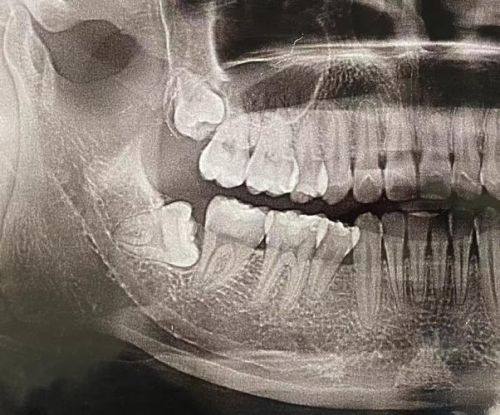

2. 精良设备支持:引进了口腔CT机、数字化口腔扫描仪、赛特丽及EMS超声洁治仪、德国kava喷砂仪、德国meleg真空消毒设备等精良设备,为医生的诊断和治疗提供精细依据,也能减少患者治疗时的痛苦和修复时间。

1. 赵明院长:毕业于浙江大学,拥有博士学位,是齿科的专职医师。他理论知识扎实,口腔诊疗技能娴熟,临床经验多,擅长各类口腔疾病的诊断与治疗,尤其在牙齿矫正方面有深入研究和大量成功实例。

2. 根管治疗:230元起